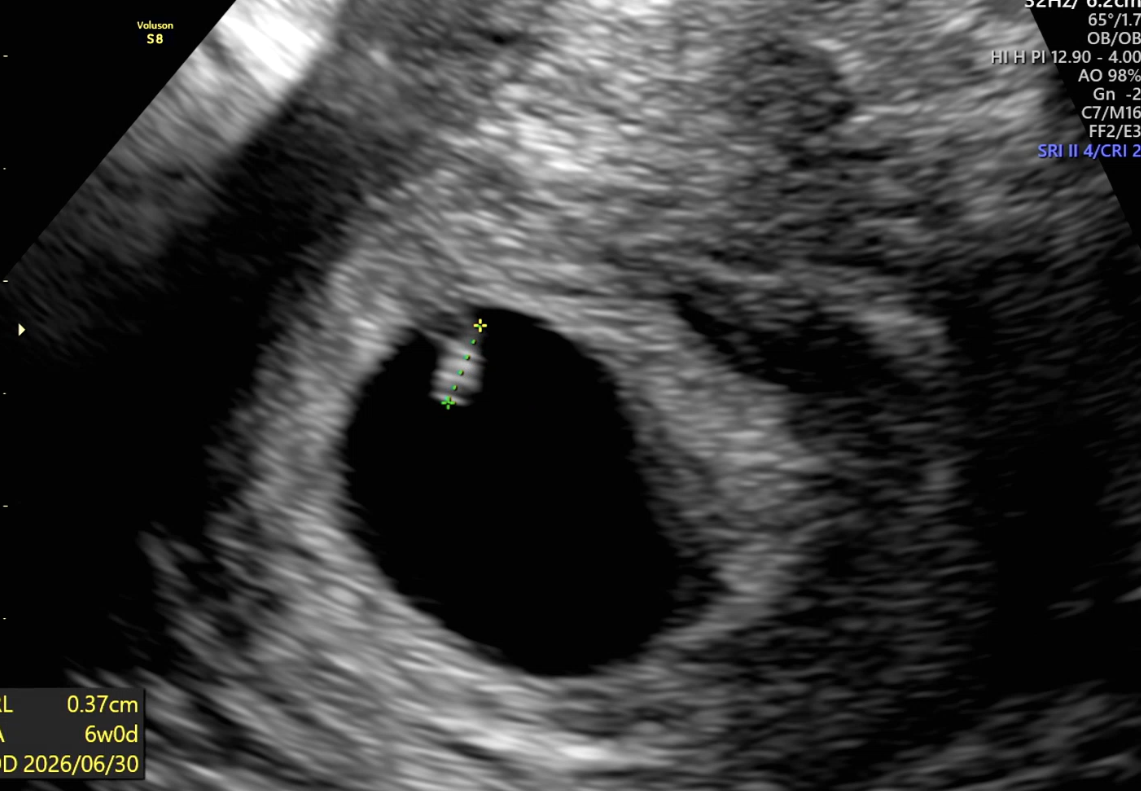

| 가슴 떨리는 임신 이야기를 공유해 주세요. | 시험관 5차에서 기적처럼 첫 착상이 되었습니다. 평소 건강에 대한 자부심이 있었기에 설마 다섯 번째까지 오게 될 줄은 몰랐고, 과정 중에는 막막한 마음이 컸습니다. 그래서 더더욱 이 결과가 믿기지 않고 감사하게 느껴졌습니다. |

| 치료 도중 느꼈던 가장 기뻤던 순간과 절망적인 것들은 무엇인가요? 잊지 못할 경험이 있나요? | 가장 기뻤던 순간은 시험관 5차에서 처음으로 착상 소식을 들었을 때입니다. 반대로, 예상보다 길어졌던 치료 과정 자체가 가장 힘들고 막막했던 시간이었습니다. |

| 난임 기간 동안 도움을 받았던 것들 중 다른 난임환자분들 위해 나눌 것이 있나요? | 착상 실패를 반복하고 계신 분들께는 PGT 검사를 한 번쯤 고려해 보시길 권하고 싶습니다. 저는 PGT 검사를 통해 첫 착상을 경험할 수 있었고, 그 선택에 대해 매우 감사하게 생각하고 있습니다. |